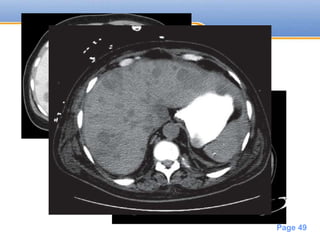

CT

• On unenhanced CT -> Hypodense

• On Enhanced CT -> non enhancing

hypodense

• The margin of the lesions can vary from

well defined to ill defined

• Hyperattenuating lesions are uncommon

Powerpoint Templates

Page 49

• #49 liver metastases may display slight peripheral enhancement with a hypoattenuating center Hyperattenuating lesions are uncommon On the portal venous phase of scanning, some highly vascular primary tumors such as renal cell carcinomas, pancreatic islet cell tumors, pheochromocytomas, melanomas, and breast carcinomas, may appear as isoattenuating to normal liver

• #50 Liver metastases, contrast-enhanced CT. Multiple hypoattenuating lesions of varying sizes are seen in both the left and right lobes of the liver, some with indistinct margins. The patient had colorectal carcinoma. CT scan showing extensive liver metastases